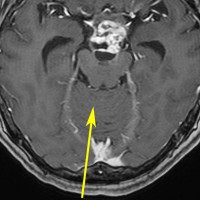

左は術前,右は手術直後のMRIです。このビデオを見て,およその手技の順番のみ把握して下さい。

松果体腫瘍へのOTAのルートです。occipital transtentorial apporachというのは黄色の矢印に沿ってガレン大静脈の下に入る方法であり,そこから松果体部を通って第3脳室内へ直線的な視野が展開します。